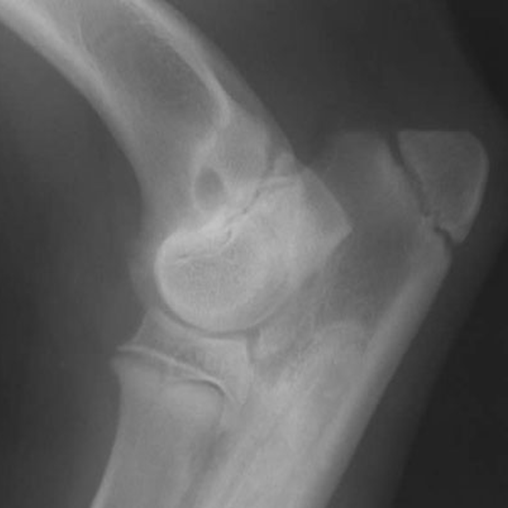

OCD in a cat